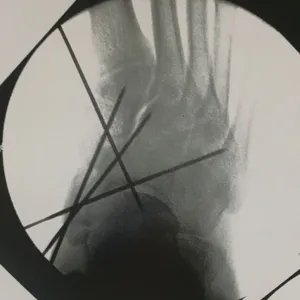

Intraop Pics Of Plantar Medial Foot Release for Chronic Exertional Compartment Syndrome in the foot